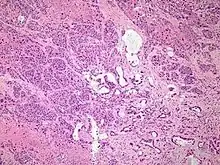

Micrograph of pancreatic ductal adenocarcinoma (the most common type of pancreatic cancer). H&E stain

Histopathology

The most common form of pancreatic cancer (adenocarcinoma) is typically characterized by moderately to poorly differentiated glandular structures on microscopic examination. There is typically considerable desmoplasia or formation of a dense fibrous stroma or structural tissue consisting of a range of cell types (including myofibroblasts, macrophages, lymphocytes and mast cells) and deposited material (such as type I collagen and hyaluronic acid). This creates a tumor microenvironment that is short of blood vessels (hypovascular) and so of oxygen (tumor hypoxia).[11] It is thought that this prevents many chemotherapy drugs from reaching the tumor, as one factor making the cancer especially hard to treat.[11][3]